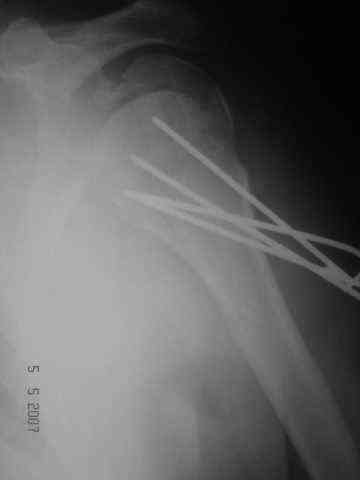

Looking at his previous x-rays, I was thinking of refixing the greater tuberosity, however got anaxillary view done today which was never done during this period and this shows non-union.

It looks like the initial injury was a head splitting fracture. Presently the patient has a non-union at the level of the anatomical neck with displaced tuberosities. I would tackle the non-union, and would try to replace the tuberosities, a difficult procedure. I would use the proximal humerus locking plate from the AO.

However, even if all goes well ( a big if!), the prognosis for regaining movement sufficient to tie his turban is poor.